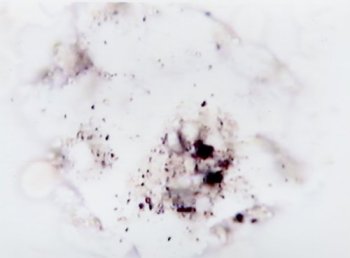

左の写真は、生の血液を撮影したもので、「尿酸結晶」と書かれたのが、通風の痛みの原因を作る「凶器」です。

ガラスの欠片のようになっているのがわかると思いますが、これが血管に刺さるのですから、たまったものではありません。

痛風に関係する病気に、「痛風性関節炎」というのがありますが、それは尿酸が関節内で結晶化し、これが関節腔に遊離すると白血球に貪食されておこる関節炎です。